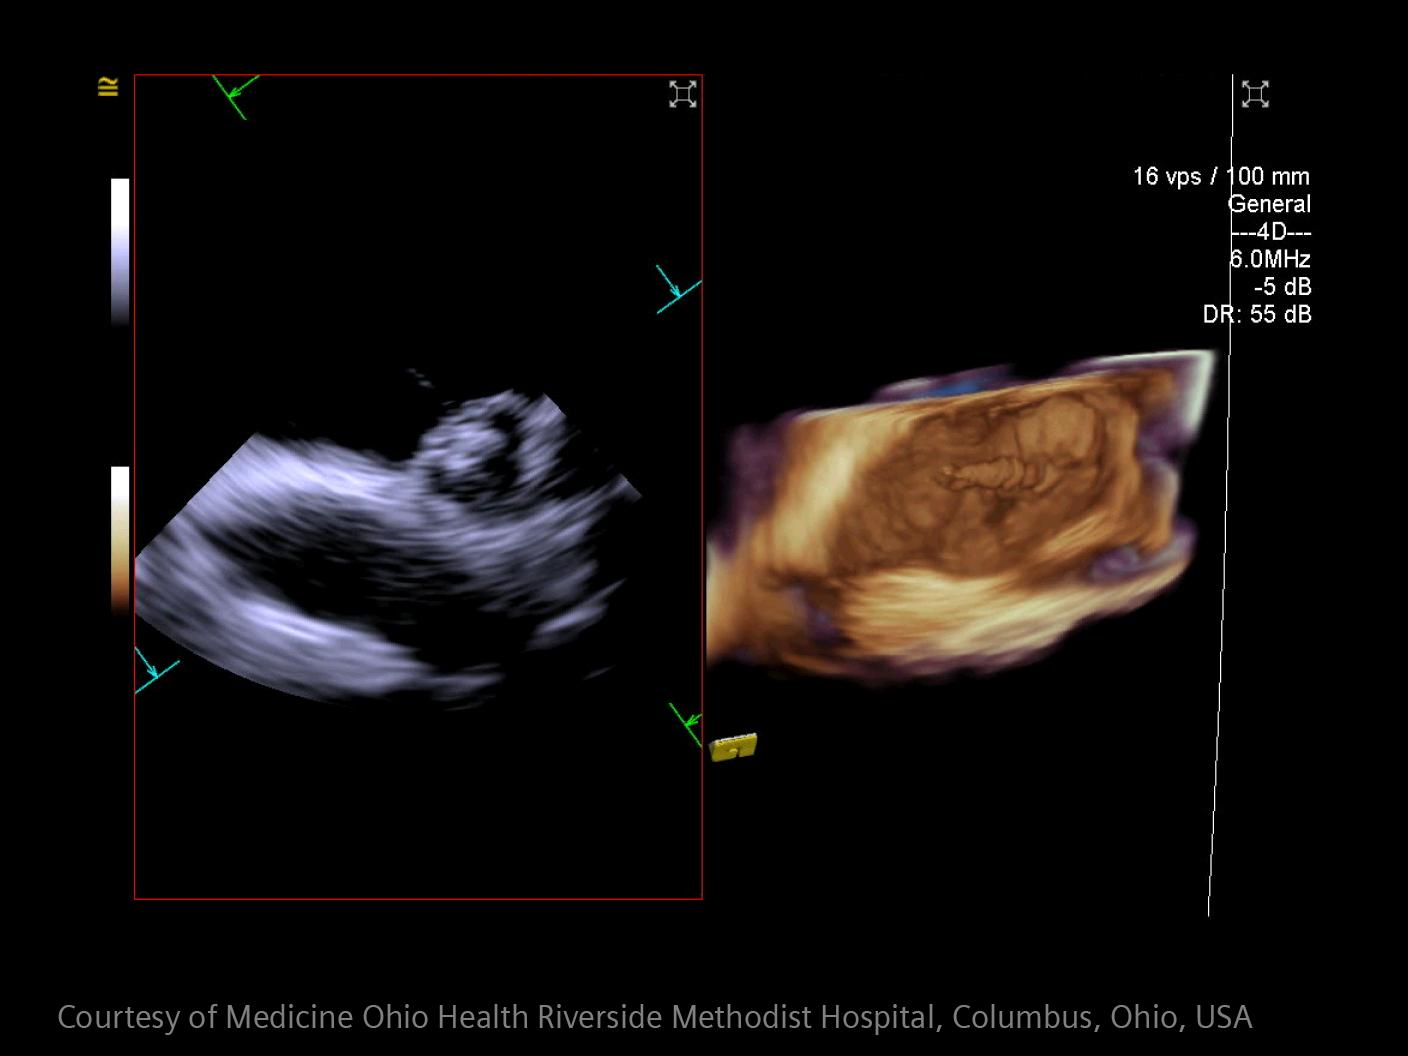

Im Bereich der Schlaganfallversorgung zählt jede Sekunde . Schnelle und präzise Bildgebung ist entscheidend, um das Ausmaß der Hirnschädigung zu beurteilen und die sofortige Behandlung einzusteuern. Angiographie, MRT, CT, Labordiagnostik und Ultraschall sind unverzichtbare Werkzeuge, um Schlaganfalltyp, -bereich und -schwere zu bestimmen. Durch technologische Fortschritte in der Bildgebung sind heute noch schnellere Aufnahmen, eine bessere Auflösung und eine optimierte Darstellung von Gehirnstrukturen und Blutgefäßen möglich. Innovationen wie Perfusionsbildgebung, Echtzeit-Gefäßkartierung und KI-gestützte Diagnostik revolutionieren die Abläufe bei Schlaganfällen und ermöglichen präzise zeitnahe Interventionen.